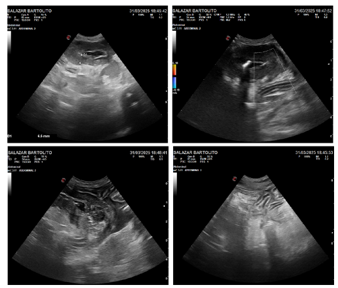

El 27 de marzo se llevó a cabo la laparotomía exploratoria, se identificó una lesión segmentaria de aproximadamente 15 cm de intestino delgado, que comprometía todas las capas intestinales hasta la serosa, y presentaba alteraciones marcadas en la coloración, consistencia y superficie. Se observó además reacción peritoneal con adherencias mesentéricas en la zona afectada. Se realizó enterectomía con anastomosis término-terminal y lavado peritoneal con solución fisiológica. El paciente permaneció hospitalizado por 48 horas, con evolución clínica favorable (Figura 2).

Para la histopatología se remitió 1 pieza de 4 x 4 x 3 cm de intestino delgado tomada intraquirúrgicamente. Macroscópicamente el segmento presentaba una configuración cilíndrica con una pared engrosada y de consistencia firme, color blanquecino y una disposición concéntrica que reducía marcadamente la luz intestinal.

El examen microscópico reveló que aproximadamente el 95% de los cortes histológicos del duodeno presentaban alteraciones morfológicas significativas, con un marcado compromiso de la luz intestinal, la cual se observaba notoriamente reducida por el engrosamiento parietal. La lesión comprometía la grasa mesentérica, serosas, capas musculares, lámina propia y mucosa con un fuerte infiltrado inflamatorio difuso; caracterizado por neutrófilos, abundantes células gigantes multinucleadas y numerosas células linfoplasmocíticas acompañadas de proceso fibrótico severo. Multifocalmente el mesenterio, capas musculares, submucosa y lámina propia mostraba acúmulos de material amorfo eosinofílico en forma de estrella junto con abundantes células inflamatorias (neutrófilos, eosinófilos, histiocitos, células gigantes multinucleadas) y material necrótico; en el centro de esta condensación se observó formas filamentosas a cilíndricas septadas con ramificaciones de 50µm de diámetro (fenómeno de Splendore-Hoeppli).

En la lámina propia y en la mucosa se evidenció un infiltrado inflamatorio mixto, acompañado de fibroplasia severa, hemorragia y congestión de los vasos sanguíneos. Se observaron escasas vellosidades intestinales y restos de estructuras glandulares, mientras que el resto de la mucosa presentaba extensas áreas de necrosis. En la luz del órgano se identificaron restos necróticos y colonias bacterianas distribuidas de manera aleatoria.

El diagnóstico clínico-patológico fue peritonitis y duodenitis transmural, severa, crónica y de carácter piogranulomatoso difuso, acompañada de fibrosis marcada y necrosis tisular, donde se identificaron estructuras hifales compatibles con un agente de tipo fúngico. Estos hallazgos permitieron establecer el diagnóstico etiológico definitivo de pitiosis entérica, atribuido al agente causal Pythium spp. (Figura 4). En paralelo, se constató una complicación bacteriana secundaria, confirmada por el aislamiento e identificación de Proteus mirabilis en el líquido ascítico.